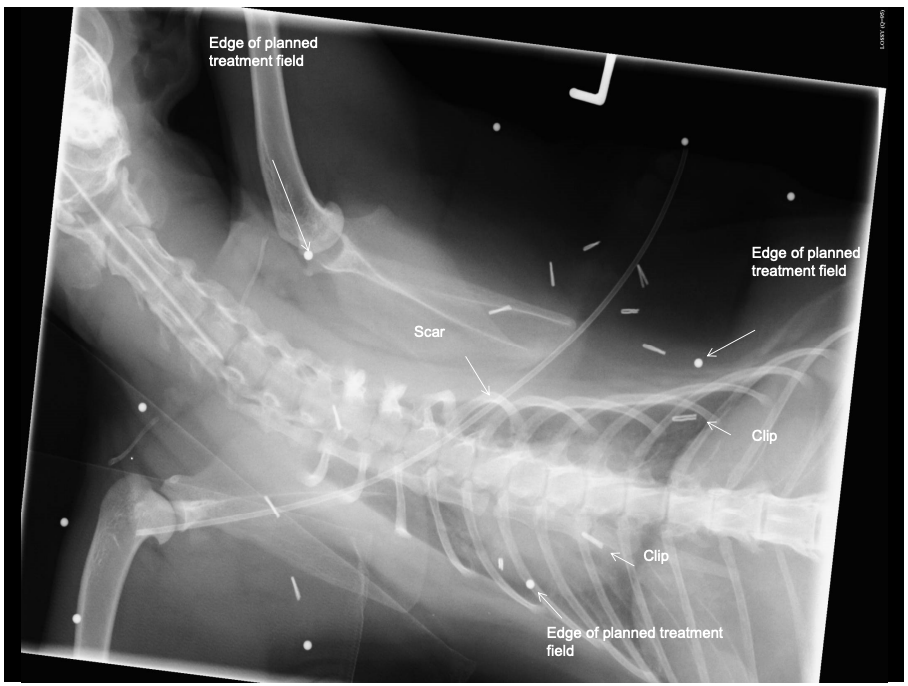

FISS: Radiotherapy

mainly used pre/ post ogg?

benifits pf radiotherapy

problem w post op radiation? 5

what couls improve survival but done less?

pre-op or post-operatively

benefit in delaying or preventing recurrence and increasing survival times

Problem with post-op radiation?

Not knowing where tumour was

Long and complex scars

post-op tissue migration (use surgical clips!)

Unable to identify microscopic disease in the gross cat

Important structures deep to tumour bed

Pre-operative radiation followed by radical surgical excision +/- post operative radiation